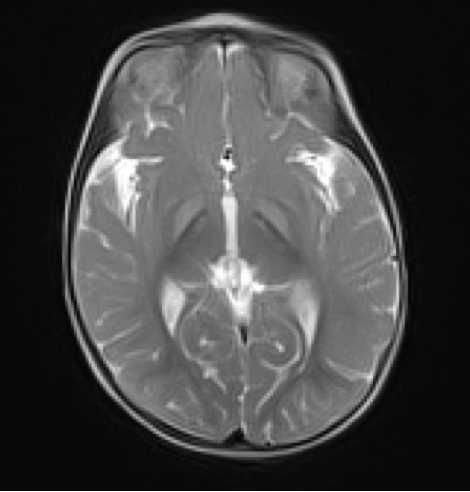

• 영상 소견

• MRI T2WI: globus pallidus, hippocampus, putamen, thalamus 등에 bilateral symmetrical high signal intensity (unconjugated bilirubin deposit)